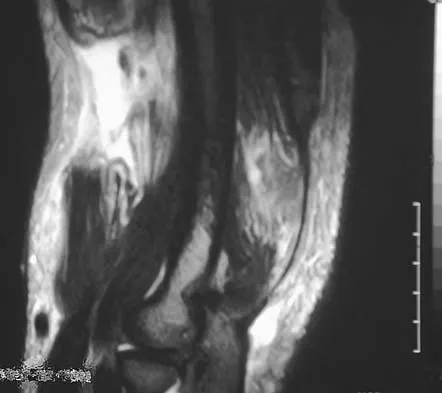

A 68-year-old man reports a 4-week history of progressive left-sided lower back and hip pain. The pain is in the posterior buttock region with radiation to the groin and to the left anterior knee region. The pain is aggravated with walking and improves with rest. There is no history of previous trauma. Radiographs are seen in Figures 14a and 14b, and MRI scans are seen in Figures 14c through 14e. What is the most appropriate treatment option at this time?

Explanation